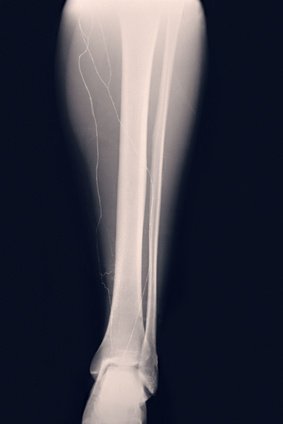

Fractura por estrés de la tibia

Imagen lesiones lesOsea estres tibia

Una grieta o solución de continuidad (fractura) en el hueso de la espinilla (tibia).

Un profesional de la medicina deportiva, como un médico especialista en medicina deportiva o un fisioterapeuta, puede diagnosticar y tratar una fractura por estrés del hueso de la espinilla. Dicho profesional podrá hacer una resonancia magnética, una radiografía o un escáner del hueso para ver el alcance de la lesión.